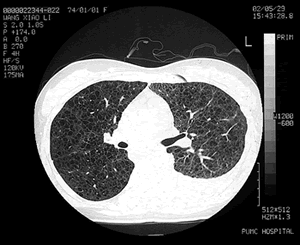

图1 胸部高分辨CT(HRCT)显示双肺弥漫性薄壁囊状改变及左侧胸腔积液

胸部高分辨CT(HRCT):双肺纹增多,紊乱,双肺弥漫性薄壁囊泡样改变(见图1)。超声心动图:少量心包积液, 腹部B超:肝、胆、胰、脾、双肾均未见异常。核素淋巴显像:考虑左侧乳糜胸为胸导管上段有瘘道进入胸腔。肺功能:一秒钟用力呼气量占预计值百分数(

LAM是乳糜胸的一个罕见原因。在北京协和医院,除特发性乳糜胸外,乳糜胸的主要原因为创伤性及结核(见表1),其他原因如淋巴瘤及丝虫病等也要注意。本例在鉴别诊断时需要仔细考虑这些疾病的可能。但由于同时合并双肺弥漫性囊状病变及气胸史,诊断的天平明显地指向罕见疾病LAM。双肺弥漫性囊性病变也需要与一些疾病相别,如肺气肿、肺间质纤维化(蜂窝肺)、囊性支气管扩张、组织细胞增生症X,及肺囊性纤维化等。根据病史及临床特点,鉴别起来并不难。HRCT在区分这些病变的特点时有突出的优势,对于了解病变类型,分布及特征很有帮助。

朱元珏教授(呼吸科):LAM较为罕见,但其临床表现如咯血、气胸、乳糜胸和呼吸困难在日常工作中经常碰到。LAM的HRCT有特征性改变,相信大家看过本例之后印象深刻。希望呼吸科医师一定要养成习惯,自己读片,而不仅仅是看放射科出的报告。LAM的囊状改变与小气道平滑肌增生后阻塞气道导致远端扩张有关,没有明显的肺间质改变。文献报道,LAM在肺移植后供体肺还可出现LAM的表现,因此,在其发病机制完全揭示之前,临床上的治疗较为困难。

本次再次推出一个罕见病是希望大家能从其诊治过程得到启发。本病表现为常见病,却是罕见病。病人在入院前经过一系列的检查和治疗,并按结核性胸膜炎治疗。在入院后,病房主管医师虽然没有诊断LAM的经验,但很快做出了正确的判断并经病理证实。其中有两点需要注意:⑴平时的鉴别诊断面要广,如本例是一个典型的LAM病例:育龄期女性/气胸/乳糜胸/双肺囊性改变,其诊断已经呼之欲出。LAM虽然罕见,大家没有什么经验,但由于平时在鉴别诊断中经常提起它,因此在理论上对它并不陌生,所以获得了迅速诊断。⑵HRCT的价值。由于本例在普通CT上不易觉察到典型的薄壁囊泡样改变,而在HRCT下却十分明显。对于任何怀疑肺气肿/肺大疱的病变,HRCT应更有优势,而且本例的肺功能提示残气量增加,在选择CT时应申请HRCT。对于这一病例的治疗,林教授也做了很好的讨论。由于目前的治疗方法并无确切依据,根据每个病人的基础状况选择治疗方案十分重要。而对于这样一个少见病,病人间以及病人和专业人士间的互相支持也很重要,因特网为此提供了很好的工具。